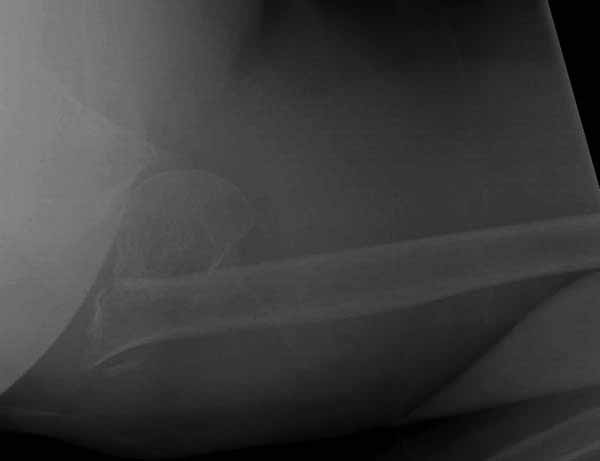

Набор мелких снимков не отражает истинную картину суставной поверхности лопатки, а также качество репозиции головки плеча. Необходимо доказать аксиальным снимком наличие покрытия головки. Правильная маркировка на рентген снимках и соответствие с выставленным диагнозом гарантирует от ошибок со стороной во время операции!

Для оценки мягкотканого покрытия и положения костных отломков, а также для изучения неврологического статуса необходимо дообследовать современными методами. Например из КТ (3D) трехмерное более информативное. МРТ и электромиография дополнит понимание ситуации и облегчит принятие правильного решения.

Здесь результат похожего случая, больная 87 лет, отягощенная сердечными делами и два года назад установка pacemaker и нескольких стентов. На третий день, сегодня утром сделали операцию. Послеоперационный псевдовывих связанный с релаксацией мышц и общим обезболиванием.